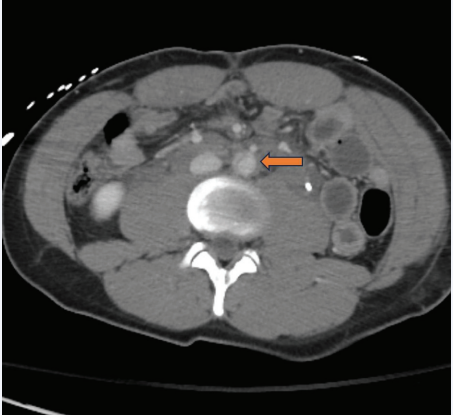

Intraoperative intravascular ultrasound [Figure 2A] and angiography [Figure 2B] evaluations confirmed a complete, circumferential intimal disruption that was highly focal. Successful exclusion of the injury was achieved by deploying a 26 mm x 33 mm Gore® Excluder® cuff (W.L. Gore and Associates, Inc., Flagstaff, Arizona) from just above the aortic bifurcation to just below the takeoff of the IMA. His immediate postoperative course was notable for continued abdominal pain. On the first postoperative day, he was taken for exploratory laparoscopy by the trauma team for ongoing abdominal pain and was found to have a bucket handle mesenteric injury requiring 2 segmental small bowel resections with primary anastomoses. One of the injured small bowel segments was perforated. He also had a serosal tear of his sigmoid colon that was treated with Lembert sutures. Additionally, he was noted to have complete transection of his rectus muscles.

Figure 2: Intraoperative intravascular ultrasound, A, which confirms complete circumferential disruption of the intima of the aorta just below the take-off of the inferior mesenteric artery (IMA), also seen on catheter-based angiography, B.